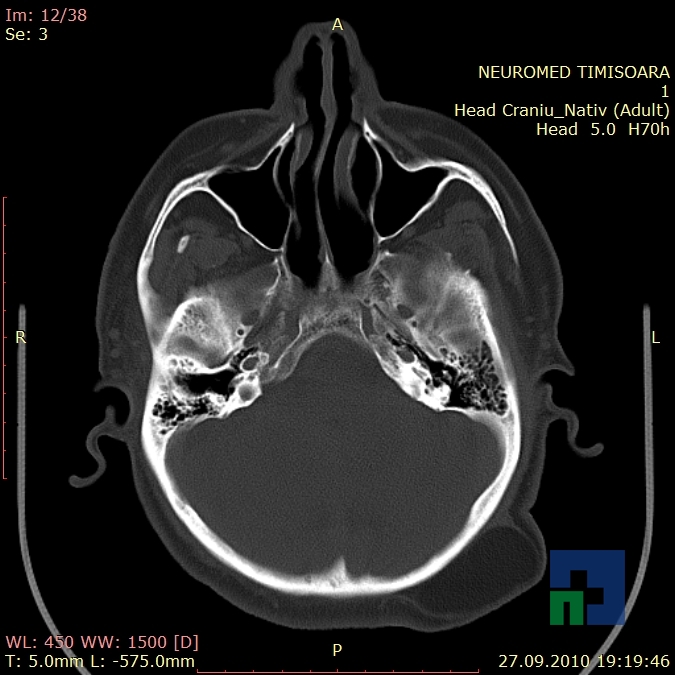

În cazul traumatismelor cranio-cerebrale:

- Diagnosticul traumatismelor de bază de craniu

- Diagnosticul fracturilor:

- Cu înfundare

- Complexe cranio-sinusale

- Complexe cranio-etmoidale

- Complexe cranio-orbitare

- Complexe cranio-faciale